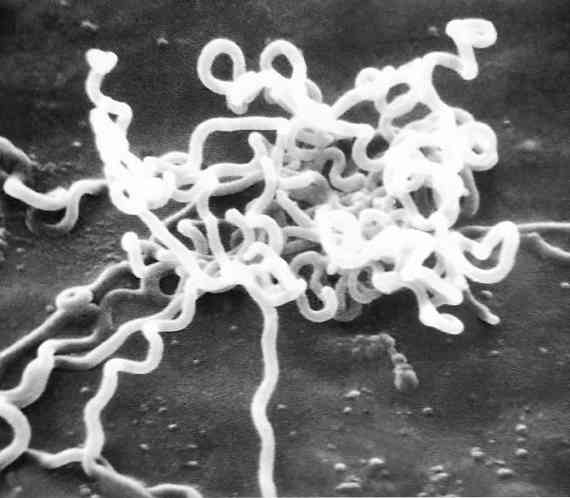

Karakteristik treponema pallidum, morfologi, habitat / Biologi | Thpanorama - Jadikan diri Anda lebih baik hari ini!

Karakteristik treponema pallidum, morfologi, habitat / Biologi | Thpanorama - Jadikan diri Anda lebih baik hari ini!